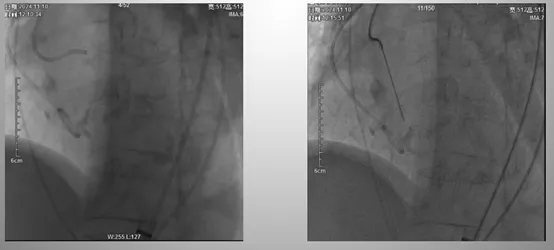

经腋动脉入路无造影剂TAVR